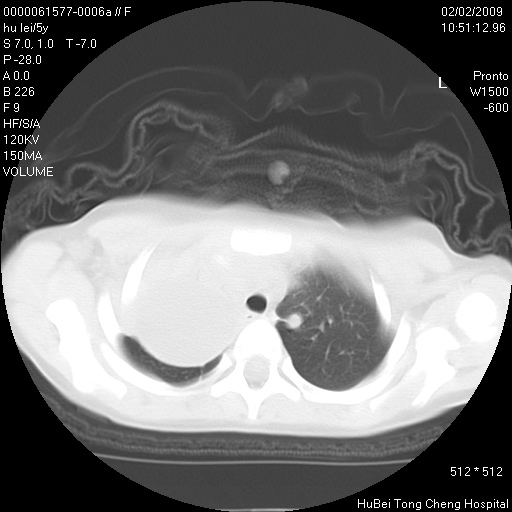

标题: PED1732:M5Y,右肺囊性占位!

患者:男,5。无明显不适,拍胸片考虑右肺囊肿。

行ct扫描,图象如下: